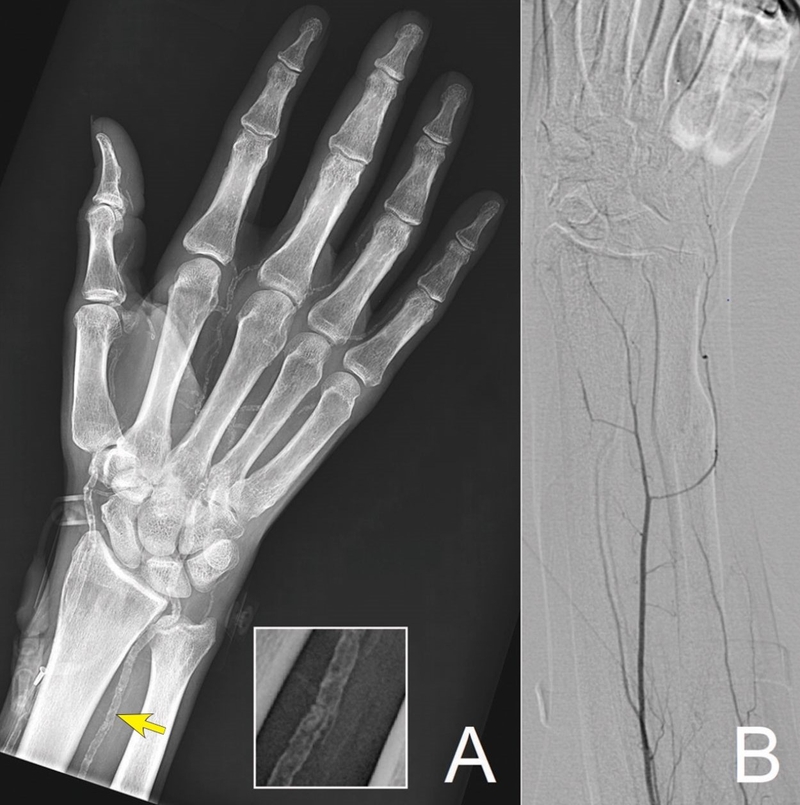

XCĐMKXV1.jpg

Xơ cứng động mạch không do xơ vữa thường được phát hiện tình cờ qua hình ảnh học